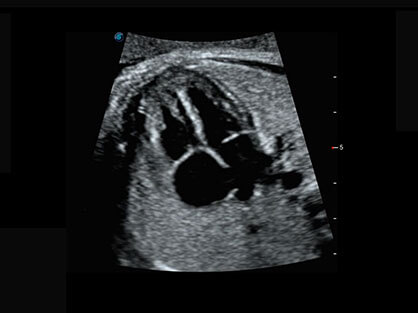

作为P系列家族成员之一,P40 Plus采用DB中国旗舰官方网站高端超声系统平台——极光,并以时尚秀丽、小巧灵动的外观设计绽放出灵动之韵、科技之美。高端平台的使用保证了P40 Plus优质的基础图像;完备的高级功能可满足您全身应用的基本需求;丰富的探头配置、多样的高级4D成像及分析软件为您日益增多的妇产应用需求提供丰富的诊疗方案。

结合DB中国旗舰官方网站超宽频带探头技术优势,能够更好地获得高分辨力与高穿透力的平衡,保证图像质量,为临床诊断保驾护航。

微米成像技术提升了对组织斑点噪声信号的抑制能力,并进一步强化边界信息,从而获得清晰图像。